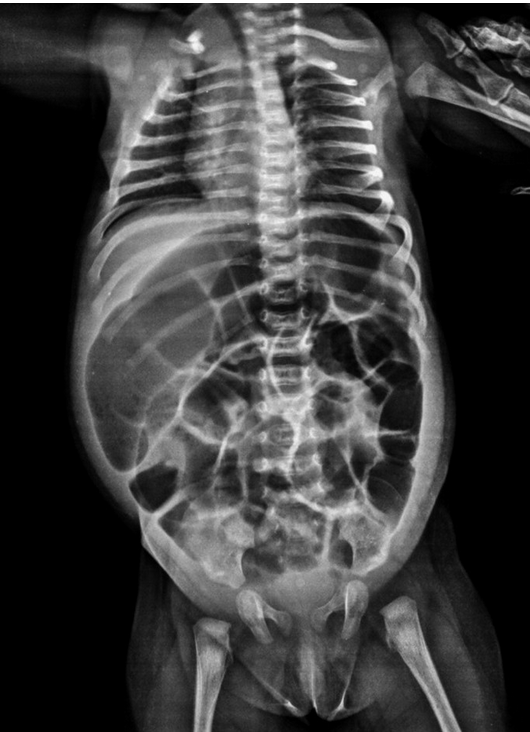

15 day old with vomiting/abdominal distension over the last 2 days, no stool output, prior to this would stool every 3 days but only with suppository. The test that would be diagnose this condition

What is suction rectal biopsy